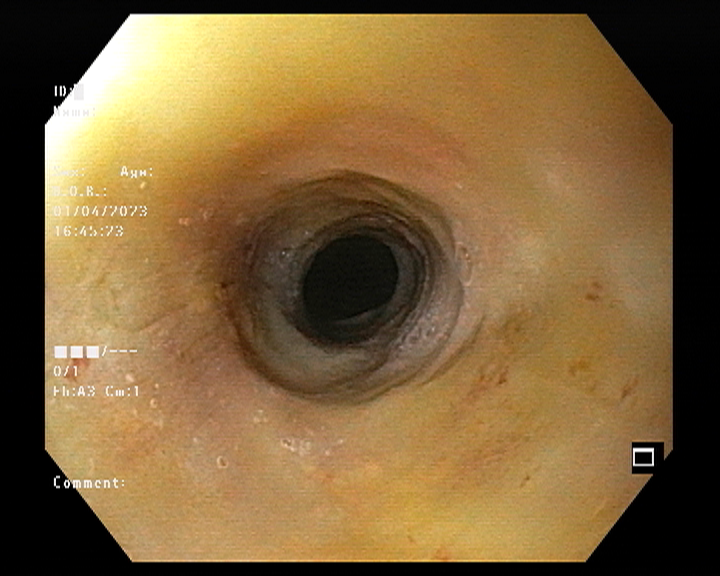

Endoscopy and colonoscopy are safe and accurate procedures used to directly examine the digestive tract and detect the root cause of chronic acidity, GERD, abdominal pain, bleeding, and bowel irregularities. These minimally invasive tests help identify ulcers, inflammation, infections, polyps, strictures, and early cancerous changes.

At Sapphire Gastroenterology Center, modern endoscopic equipment ensures precise diagnosis and, when required, therapeutic intervention during the same procedure. Based on findings, targeted treatment plans are created, including medication, diet guidance, and preventive strategies. Early diagnosis through endoscopy and colonoscopy plays a crucial role in preventing serious complications and improving long-term digestive health.